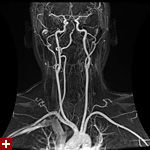

once i got back home and checked out my scans in osirix (the mac os x application to view DICOM medical imaging slides), i was blown away. talk about invasive: you haven't seen intimate until you've looked at photos of the inside of your body. the coolest part is since the scans were done in cross-sections, i can animate the scans so it looks like the beam is passing through my neck and head (all 800+ images). i've always known that inside my body was all sorts of muscles and veins and organs, but i guess i was hoping for something less messy, maybe circuit boards and memory chips instead. i know MRI's were first used in the late 60's, but this is my first time experiencing the technology in-person and it's pretty amazing. talk about futuristic! to be able to see with so much detail the insides of my body without having to cut me open! if scientists can do this, what else can they do? my only regret is they only imaged me from my shoulder up. i'd love to have a full-body scan. maybe i can fake some sort of internal injury and get my doctor to okay the procedure. i recommend anyone who's never had an MRI done to do so when they have the chance.

speaking of doctors, the main reason why i was at MGH this morning was for a follow-up appointment with my doctor. he basically told me that my MRI scans were fine as well as my blood work (he wrote me a letter a few weeks ago, so i already knew the news). since the pain in my neck had already disappeared,

i wasn't disappointment that we never figured out what was the cause. however, i did want to talk to him about the muffled hearing i've been experiencing in my left ear since as far back as october. he checked my ear and it seemed normal: no inflammation, no perforated eardrum. a look down my throat revealed nothing as well. lacking anymore clues he decided to throw a bunch of drugs at me to see if it'd clear up my sinuses, which seemed to be the root of the problem. besides taking some claritin-D (pseudoephedrine sulfate & loratadine), he also told me to take some sudafed as well (pseudoephedrine hydrochloride), a combination of antihistamine and decongestant. that's followed my some afrin nasal spray (oxymetazoline hydrochloride) plus the prescription strength nasal spray flonase (fluticasone propionate).